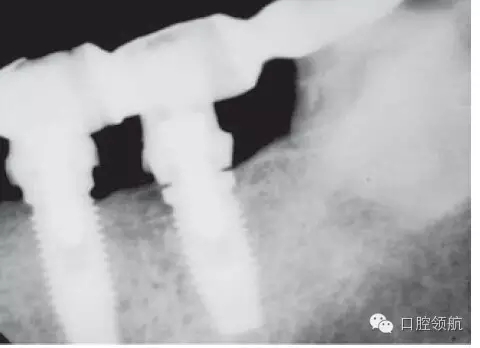

另外一個方面,深的袖口將妨礙修復(fù)體完全就位(圖9.26)。通??梢酝ㄟ^放射學(xué)檢查,確認(rèn)修復(fù)部件的就位情況,包括種植體與基臺的連接部分。即使是內(nèi)連接,轉(zhuǎn)移體或者其他修復(fù)部件也會因深袖口而不能就位。以下技術(shù)可以用于解決這些問題:可以在局部麻醉下,插入喇叭狀或者外展的基臺,以非手術(shù)的方式擴(kuò)大袖口(圖9.27 a,b),然后再通過放射學(xué)檢查確定部件的完全就位。組織會受壓發(fā)白,15分鐘后,軟組織將會擴(kuò)張,以允許理想修復(fù)部件的就位,這樣治療將得以繼續(xù)。有時,需要在鄰面做兩個小切口,以緩解袖口軟組織張力(圖9.28 a,b)。通常不需要縫合。一旦袖口組織塑形完成,可運用最佳塑形的臨時(圖9.29)或最終部件(圖9.30),來維持理想的軟組織外形。

圖9.26 放射學(xué)影像顯示,在外六角連接的種植體上,基臺沒有完全就位。